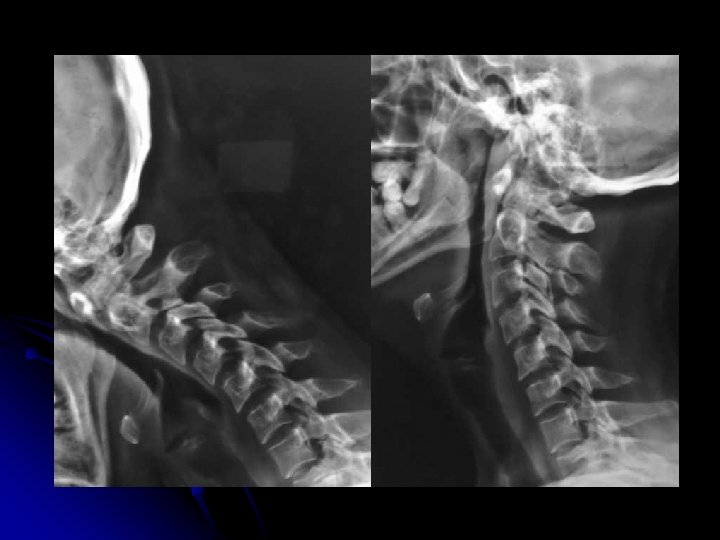

l Clichés dynamiques l Profil l Position même que pour le profil d'ensemble/ l l Flexion maximale, sans aide et sans dépasser le seuil douloureux l Extension maximale sans aide et sans dépasser le seuil douloureux Centrage, rayon directeur, et critères de réussite, sont identiques au profil d'ensemble l Précautions: l Patient conscient l Médecin présent l Absence de contre-indication neurologique l Un délai de 10 à 15 jours par rapport au traumatisme est habituellement à respecter.

Neutre Flexion Extension